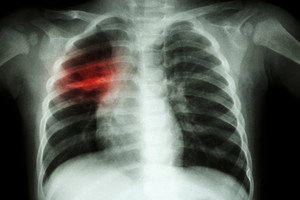

Tuberkuliozė plinta oro lašiniu būdu nuo atvira tuberkulioze sergančių žmonių. Tuberkuliozės simptomai priklauso nuo pažeisto organo. Dažniausiai tuberkuliozė pažeidžia plaučius. Jei pasireiškia kosulys, trunkantis ilgiau nei 2 – 3 savaites, tuomet rekomenduojama pasitikrinti dėl tuberkuliozės.

Tuberkuliozė (TB) – užkrečiamoji liga, kurią sukelia bakterija Mycobacterium tuberculosis. TB bakterijos dažniausiai puola plaučius, bet jos gali pažeisti bet kurią kūno dalį, pavyzdžiui, inkstus, stuburo ar galvos smegenis. Negydoma tinkamai tuberkuliozė gali būti mirtina.

Žmogui įkvėpus tuberkuliozės bakterijų, jos nusėda plaučiuose ir pradeda daugintis. Iš plaučių per kraują jos gali patekti į kitus organus, pavyzdžiui, inkstus, stuburo ir galvos smegenis.

Tuberkuliozės simptomai pasireiškia, kai tuberkuliozės bakterijos pradeda organizme daugintis. Plaučių tuberkuliozė gali sukelti tokius simptomus:

kosulį, trunkantį 3 ar daugiau savaičių;

kosėjimą su skrepliais ar su krauju.